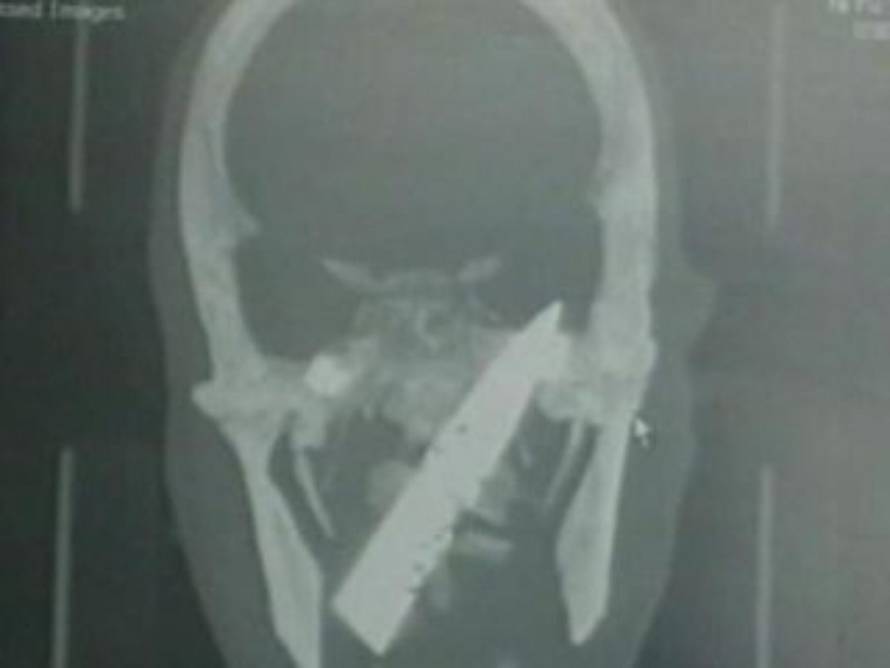

Muškarca su prije više od četiri godine uboli nožem u glavu tijekom jedne pljačke. Liječnici nisu primijetili da mu je nož 'zapeo' u mozgu. Operirali su ga prošli tjedan